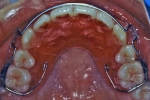

ホーレータイプ

多くの場合後戻りしやすいのは前歯部なので、ここを重点的に押さえて臼歯部はフリーにしてあるタイプをホーレータイプのリテーナーと言います。ホーレータイプもベッグタイプも構造的には歯を動かす装置が付いていない床矯正装置と言えます。